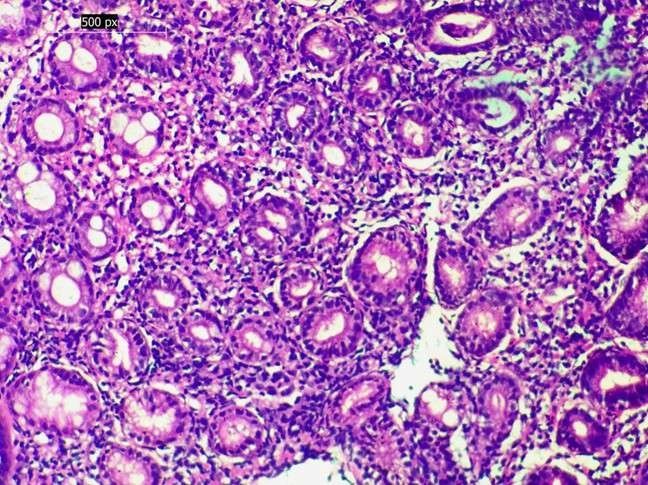

The histological findings were found to be mainly due to inflammatory lesions, which comprised 70 percent of all the biopsies, mostly representing chronic gastritis. Malignant lesions constituted 24% of cases, the most common type of which was gastric adenocarcinoma, and then the squamous cell carcinoma of the oesophagus. Benign neoplasms were isolated to gastric polyps (4.5%), and the premalignant changes were rare (1.5%), including intestinal metaplasia, dysplasia, and Barrett's oesophagus with dysplasia (see Table 2, Figures 1 and 2).

Figure 1. (A – B). Histological features of inflammatory lesions. (A) Chronic gastritis showing dense mononuclear infiltrates in the lamina propria (H&E, 200×). (B) Chronic gastritis with Helicobacter pylori organisms adherent to the gastric epithelium (H&E, oil immersion).

Figure 2. Premalignant change in chronic gastritis. Chronic gastritis with intestinal metaplasia, characterised by replacement of gastric epithelium by intestinal-type columnar cells with goblet cells (H&E, 400×)